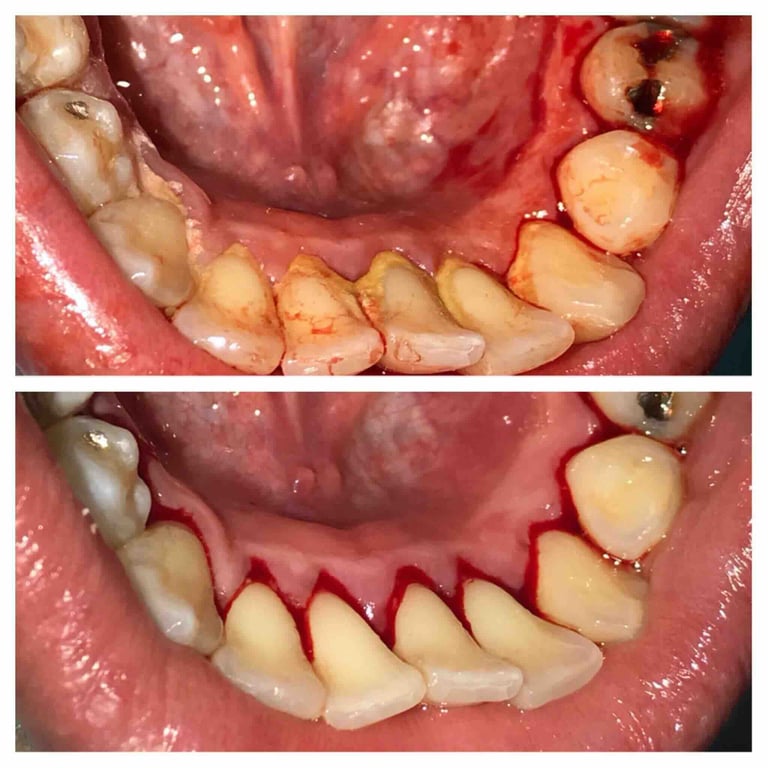

Deep cleaning, also known as scaling and root planing, is used to treat gum disease by removing plaque and bacteria from below the gum line and smoothing the tooth roots to help gums heal properly. Depending on the severity of the condition, the treatment may be completed in sections (such as half-mouth or quadrant visits) to ensure comfort and thorough care. After deep cleaning, ongoing periodontal maintenance visits every 3–4 months are essential to keep gum disease under control, as regular cleanings are not sufficient once periodontal issues are present.

Treatment Results

Scaling — removing buildup from below the gumline

Root planing — smoothing the roots to help gums heal